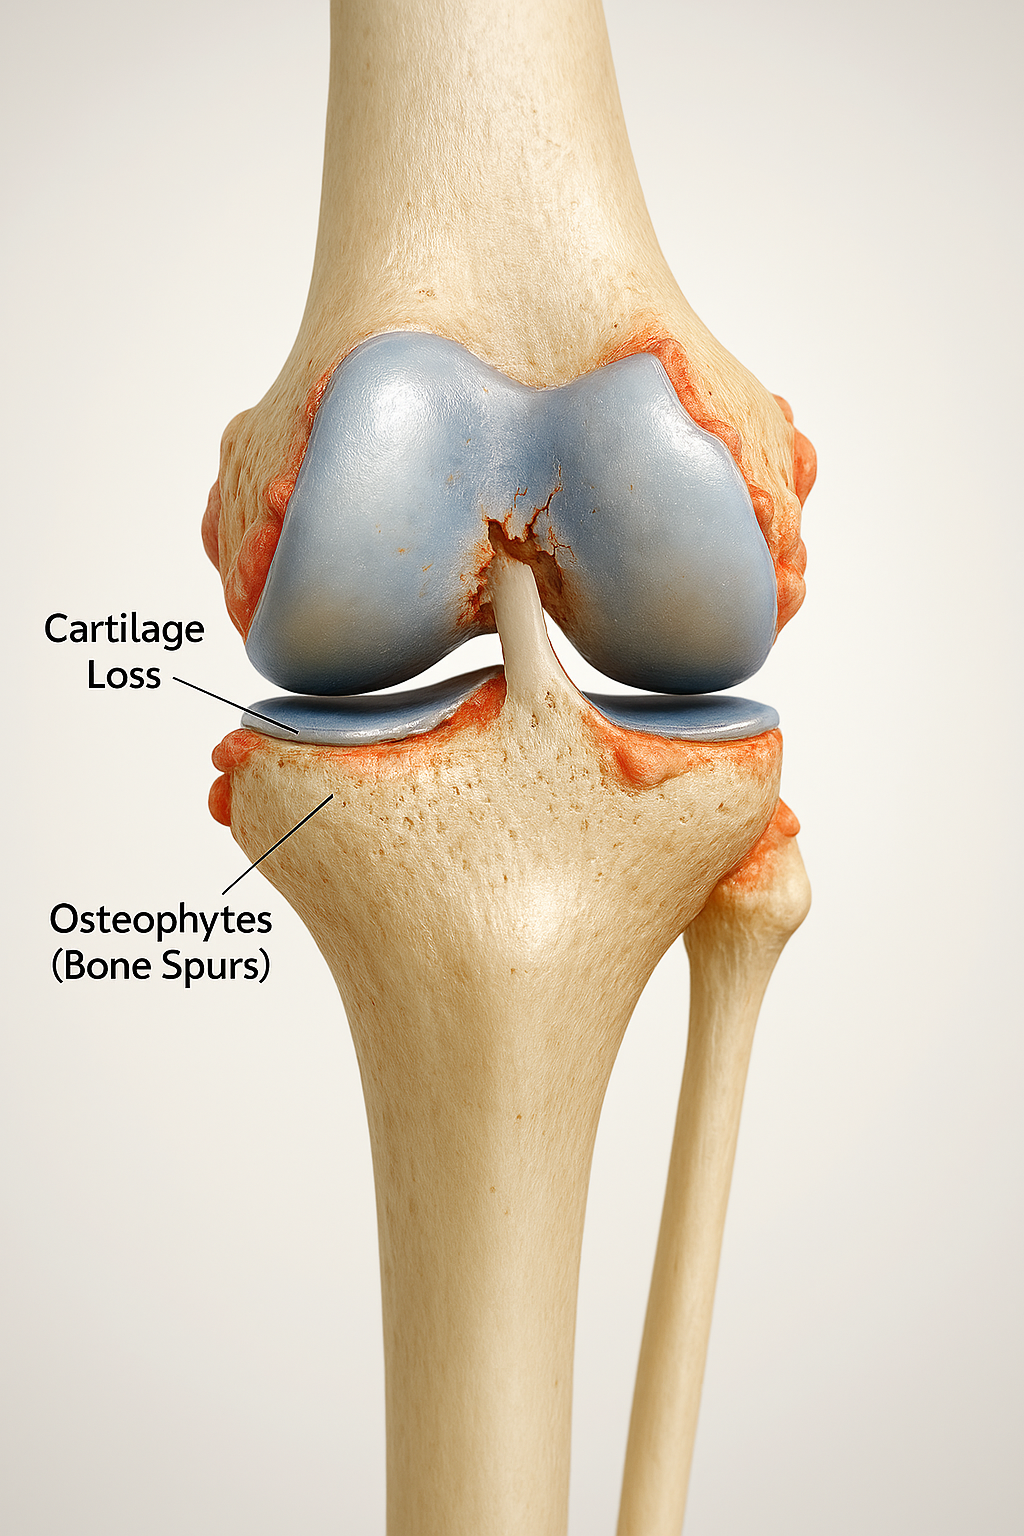

A artrose de joelho é uma das doenças reumáticas mais frequentes e incapacitantes, especialmente após os 50 anos. Trata-se de um processo degenerativo que compromete